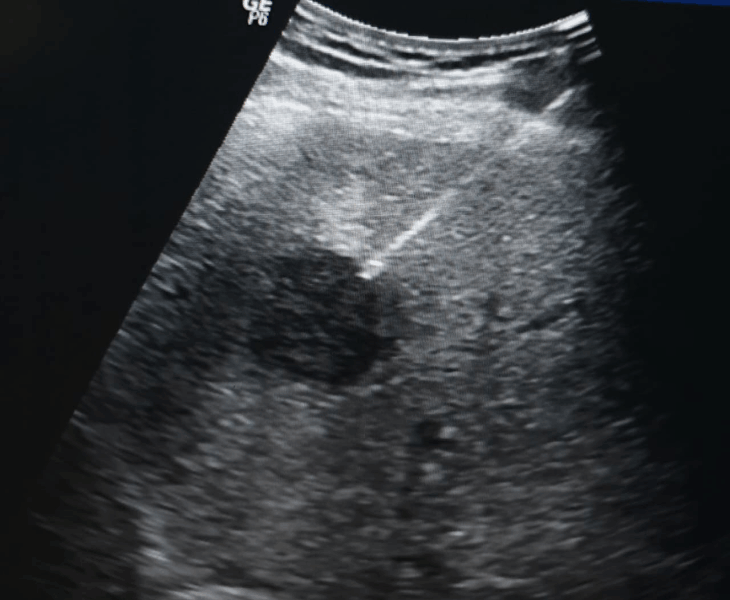

Marker Placement

USG‑guided marker placement to help surgeons and oncologists target lesions precisely.